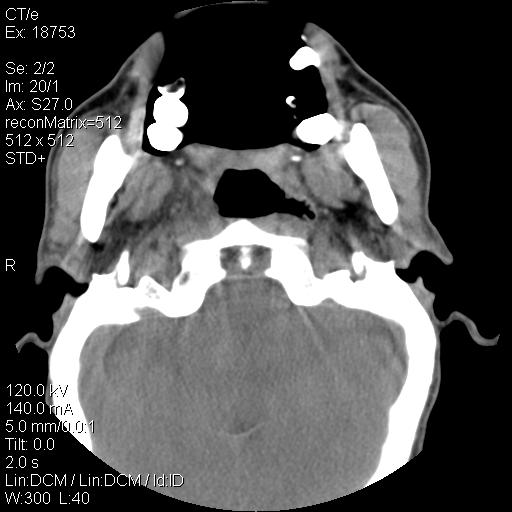

标题: CT21693:男 58岁 右侧咽部疼她2天余 PE:右侧扁桃体肿大 压痛 [打印本页]

标题: CT21693:男 58岁 右侧咽部疼她2天余 PE:右侧扁桃体肿大 压痛

右化脓性扁桃体炎症伴咽后壁脓肿形成.

结合病史,考虑感染性病变;建议抗炎治疗复查排除肿瘤性病变。